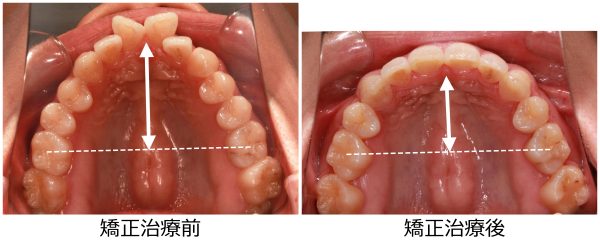

27歳 女性 「 ねじれ歯、出っ歯を治したい 」 ( 翼状捻転 )

27歳の 女性です

「 ねじれ歯 と ”出っ歯” を治したい 」との事で来院されました。

上の前歯が ねじれて 傾斜しているため

前歯だけが 目立ってしまいます。

前歯のねじれを鳥の翼に例えて、翼状捻転と呼ばれる状態です

前歯も傾斜しているため ”出っ歯” 感も強いです。

とにかく「ねじれて ”出っ歯”な 前歯が目立つのが嫌だ」との事でした。

捻じれと 出っ歯を治したいとの事で矯正治療を開始しました。

翼状捻転を伴う 上顎前突症 です。

ねじれと ”出っ歯”を治したいとの事で

上下左右の 抜歯を行い 前歯を後方に移動させました。

2018年の7月4日にスタートして 2019年の10月16日に 終 了しました。

治療期間は 15か月でした。

抜歯により、前歯の捻じれと 出っ歯感が解消しました。

前歯は大きく下がりました。

前歯のねじれは改善し、大きく下がりました

前歯が大きく下がったことで、口もとの 印象が 大きく変わり

口もともスッキリと変化しました。

素敵な笑顔になりました! (#^.^#)

ありがたいことです。

27歳 女性 叢生を伴う 上顎前突症 治療期間15か月 唇側矯正装置(ホワイトワイヤー)を使用した上下顎第一小臼歯抜歯治療 参考治療費 約65万円 (精密検査から終了まで) 矯正治療に伴う副作用の歯肉退縮、知覚過敏、失活、歯根吸収などは認められませんでした。